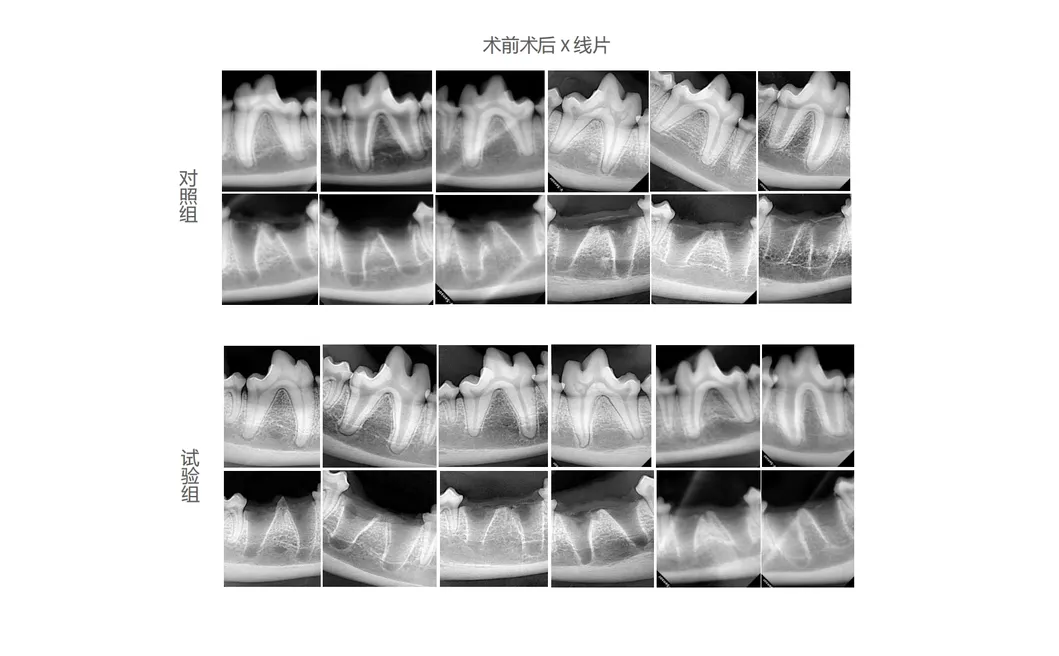

In this study, dogs were chosen as the experimental subjects to evaluate the effectiveness of revolutionary dental tools. The control group employed traditional manual tooth extraction devices, while the treatment group experienced the state-of-the-art Pneumatic Dental Elevator Kit. Critical factors including physiological parameters, duration of extractions, and soft tissue healing were meticulously documented and analyzed statistically.